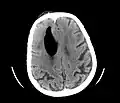

Pneumocephalus and comminuted fracture of the frontal sinus

Pneumocephalus is the presence of air or gas within the cranial cavity. It is usually associated with disruption of the skull: after head and facial trauma, tumors of the skull base, after neurosurgery or otorhinolaryngology, and rarely, spontaneously. Pneumocephalus can occur in scuba diving, but is very rare in this context.

CT scans of patients with a tension pneumocephalus typically show air that compresses the frontal lobes of the brain, which results in a tented appearance of the brain in the skull known as the Mount Fuji sign.[1][2][3] The name is derived from the resemblance of the brain to Mount Fuji in Japan, a volcano known for its symmetrical cone. In typical cases, there is a symmetrical depression near the midline (such as the crater of a volcano), due to intact bridging veins.[3] Its occurrence seems to be limited to tension pneumocephalus (not occurring in pneumocephalus without tension).[4] The sign was first described by a team of Japanese neurosurgeons.[5]